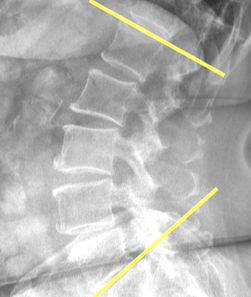

Sacral Slope (SS)

Ferguson’s Line

Ullman’s Line

Mcnab's Line